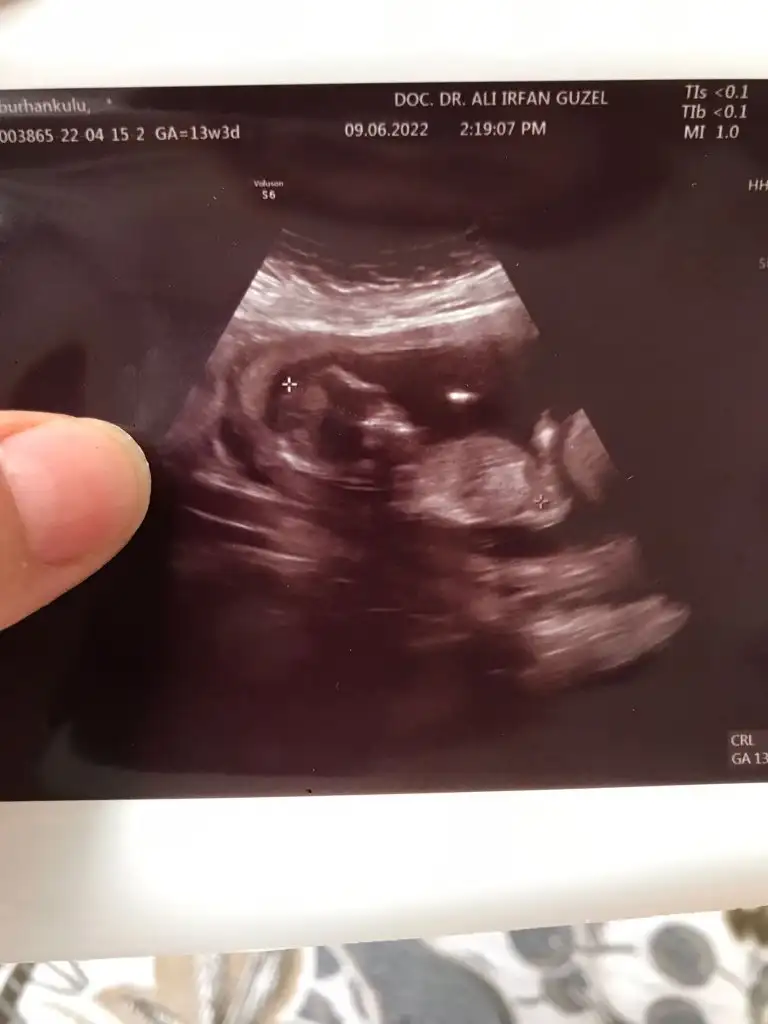

Merhabalar, rica etsem benim yeğenim için de tahminde bulunur musunuzz ☺️ 13+3 karından usg

Eklentiler